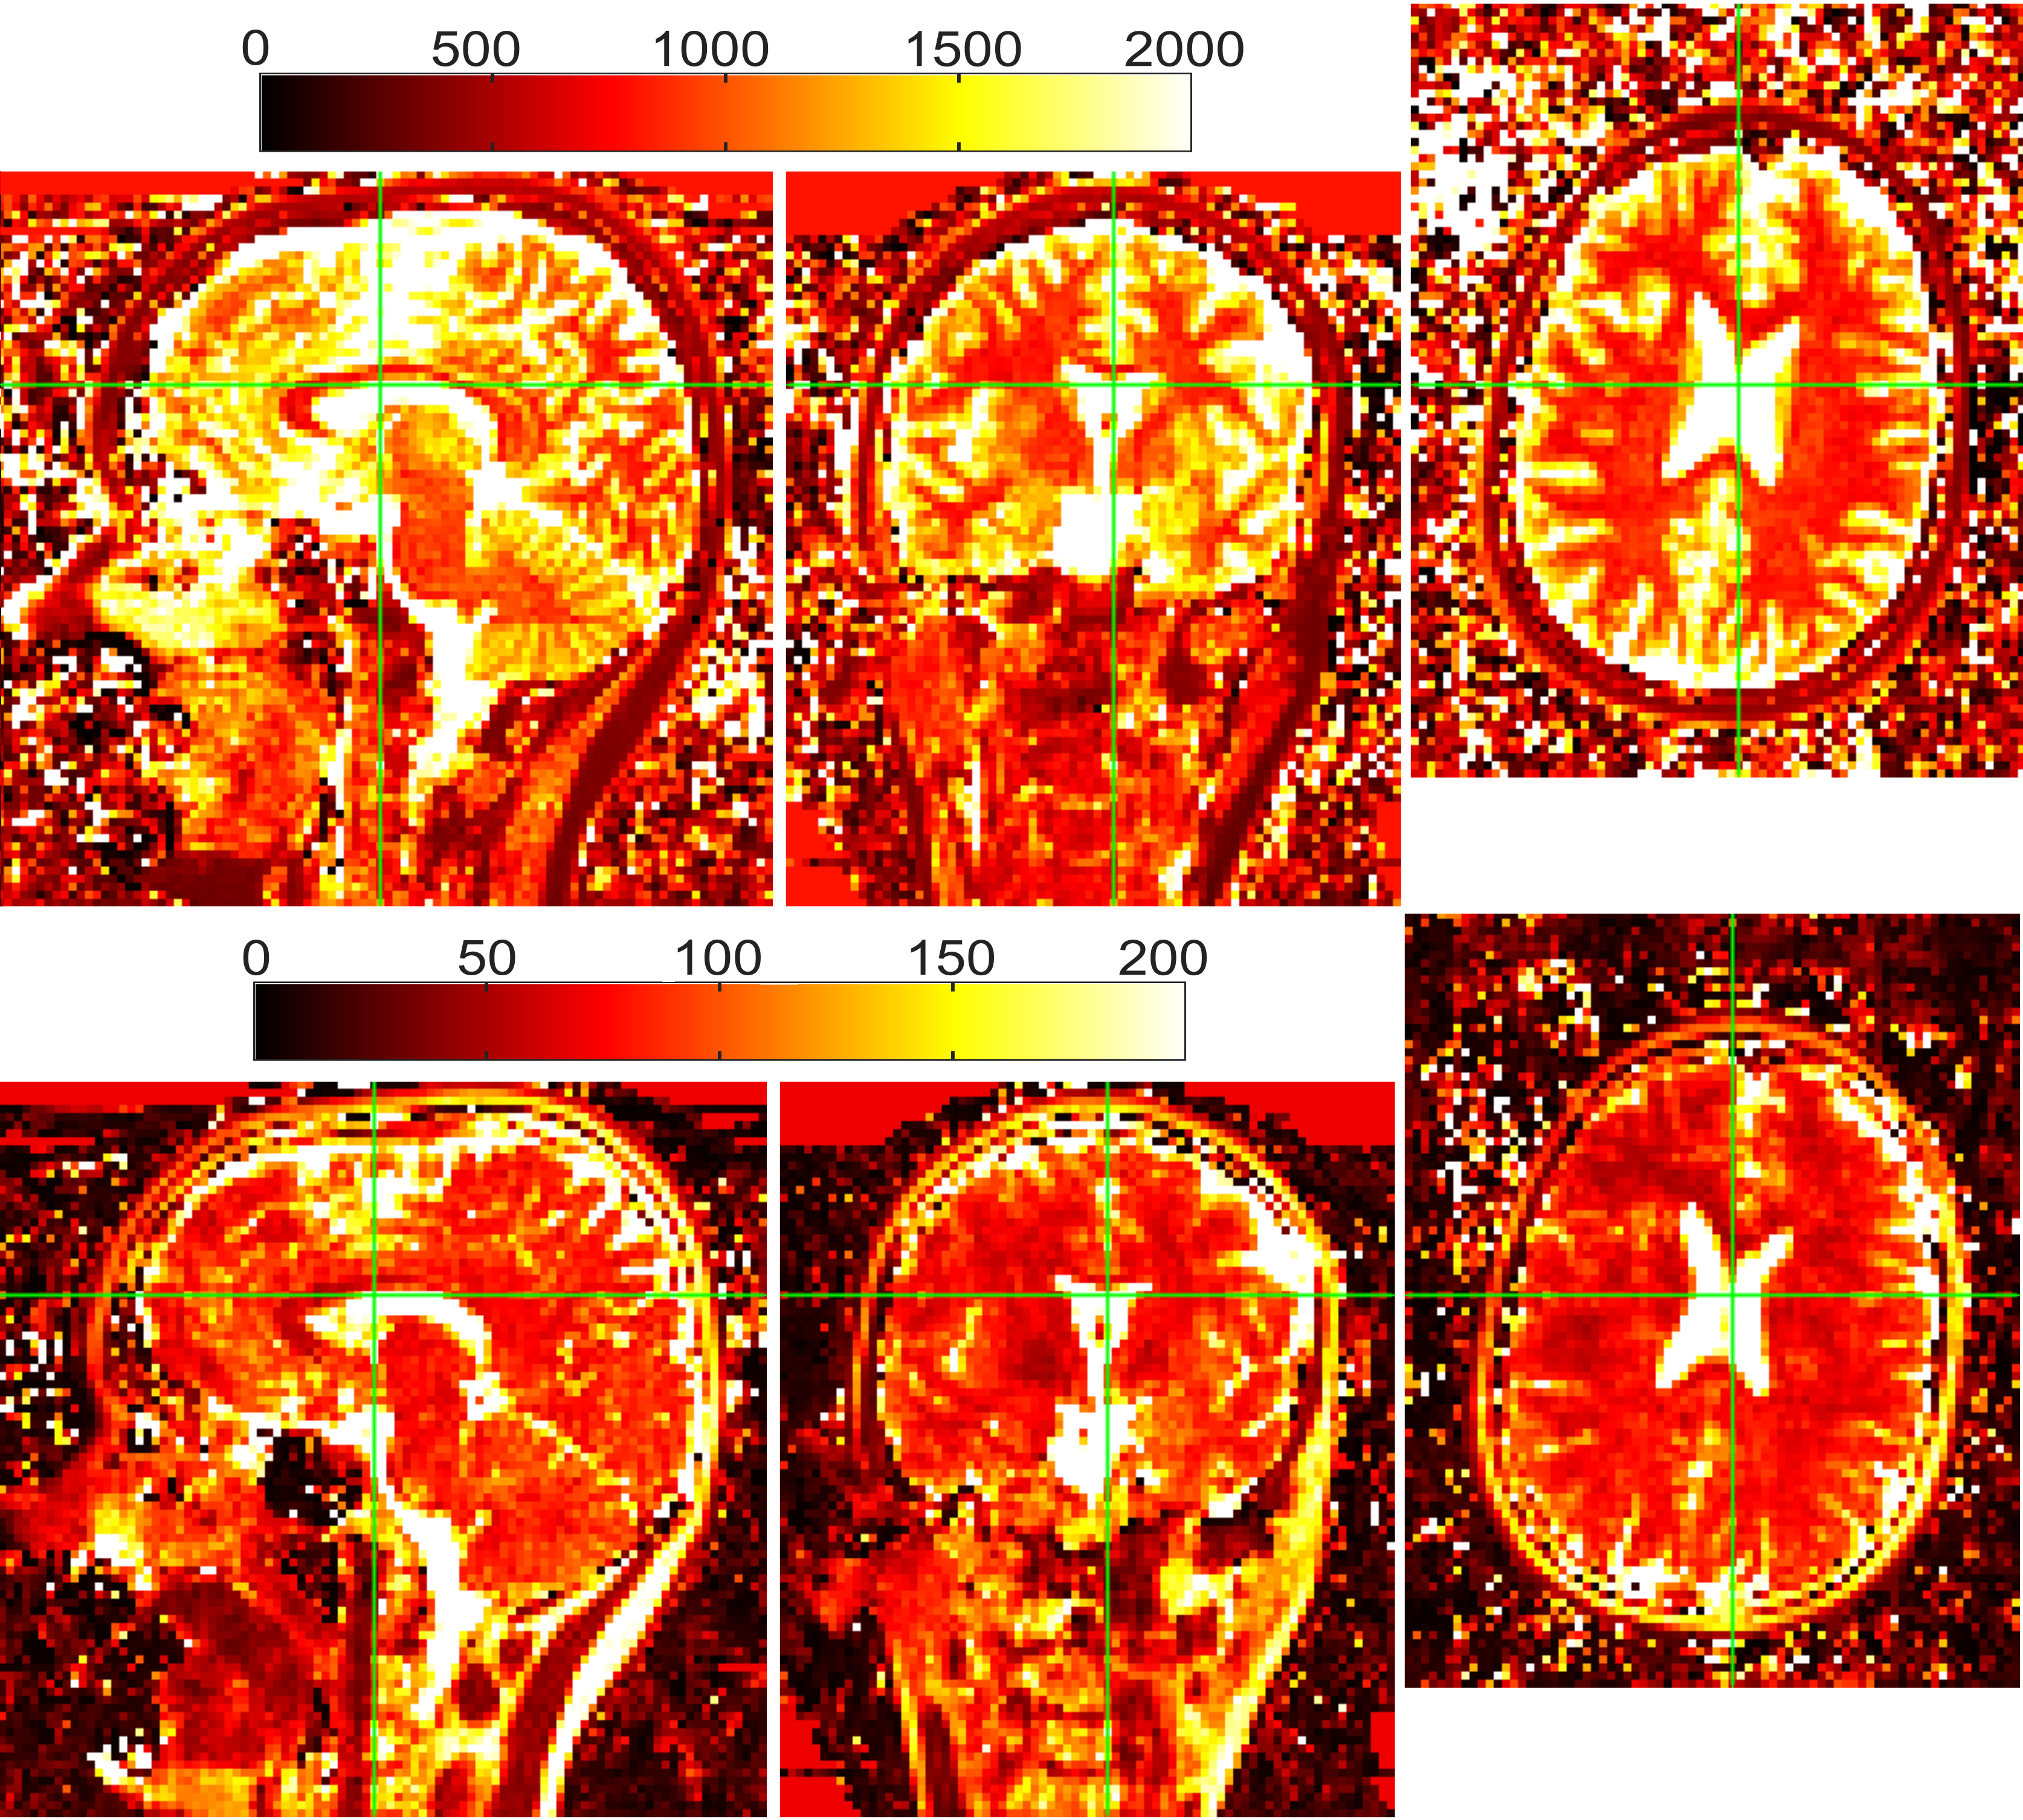

4.4 In-vivo scan

Figure9 shows the T1subscript𝑇1T_{1} and T2subscript𝑇2T_{2} map of the in-vivo acquisition. The reconstruction was performed for each FE line along the SI orientation. All the FE lines were reconstructed successfully. There are no visible artefacts related to undersampling and T1subscript𝑇1T_{1} and T2subscript𝑇2T_{2} maps are in the range expected in the human brain.

Refer to caption

Fig. 9: Aagittal (left), coronal (center) and axial (right) view of T1subscript𝑇1T_{1} map (Top) and T2subscript𝑇2T_{2} map (Bottom) (ms) of a healthy volunteer obtained with an 32-fold accelerated 3D IP-FSE scan. The green line shows the slice selected in each of the three dimensions.The SI (FE) dimension is cropped to focus on the Subject’s head.